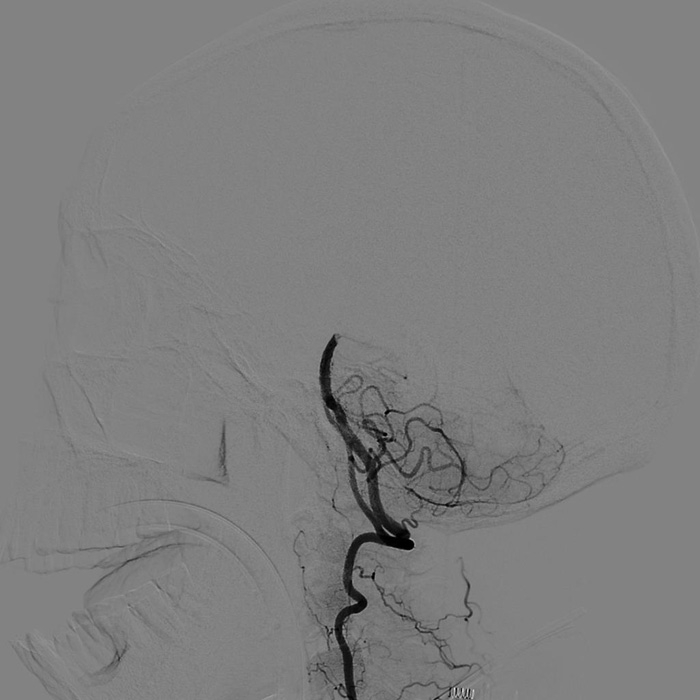

??? 22:10? 王大伯病情進(jìn)一步加重,神經(jīng)外科戴偉民主任醫(yī)師團(tuán)隊(duì)、麻醉師和介入室的醫(yī)護(hù)人員全部已經(jīng)到位。全腦血管造影顯示栓塞部位在基底動(dòng)脈末端,雙側(cè)小腦上動(dòng)脈及雙側(cè)大腦后動(dòng)脈開口處完全閉塞。

手術(shù)前血管造影提示雙側(cè)小腦上動(dòng)脈及雙側(cè)大腦后動(dòng)脈開口處完全閉塞